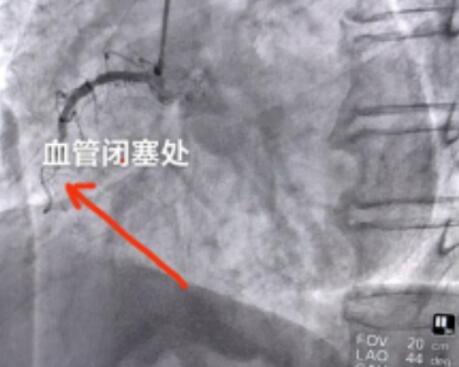

来院后,“120”直接将患者送到介入导管室,由副院长林生庚带领的胸痛中心团队立即给患者行冠脉造影,影像示右冠脉中段闭塞,随即给患者行右侧冠状动脉支架植入术。手术后患者症状即刻缓解,自主心律恢复,未再发作胸闷、心悸不适等症状。